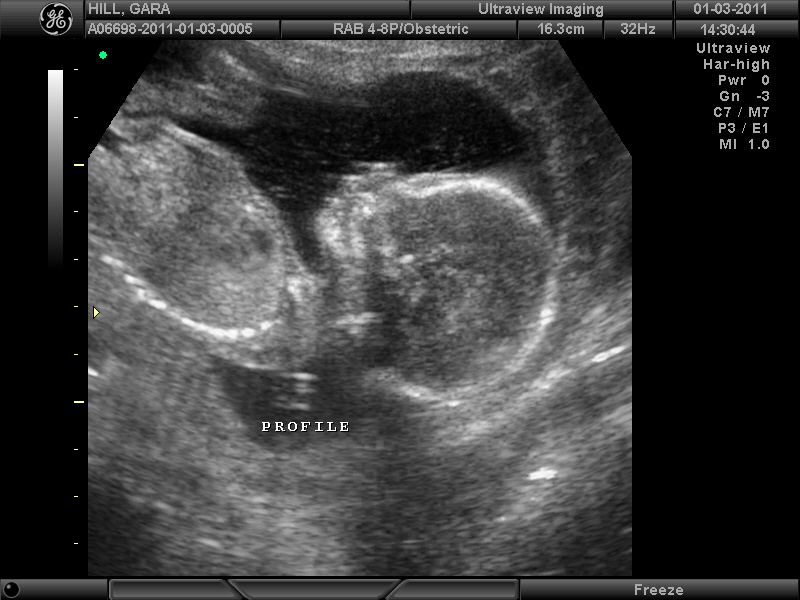

Maryn Rochelle Hill - due 6/11/11!  I will do a whole separate post on her name, but I'm so glad that Brandon and I went into this whole thing two years ago with one boy and one girl name.  We were a little stumped on what to call H2 if she had been a boy!

We had a "quickie" ultrasound at 17 weeks (the above pictures are from it), and they told us then that the baby was a girl.  I actually ran and did it while Brandon stayed here with Travis so I just kept my eyes closed so that we could open the envelope together at home.  She said she was 100% sure on January 3rd, but I was keeping that pretty close to the vest until we had our 20 week ultrasound which was this morning.  I had seen too many stories of babies sprouting penises during that window.  :)  We loved hearing that we are for sure having a baby girl, but more importantly that all of her measurements and organs were all right on track.  She measured 9.2 inches and 13 oz. today.  We are all thrilled and can't wait to complete our family with Miss Maryn.